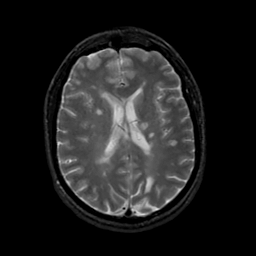

MR Study #19, August 25, 1991 -- Slice #30